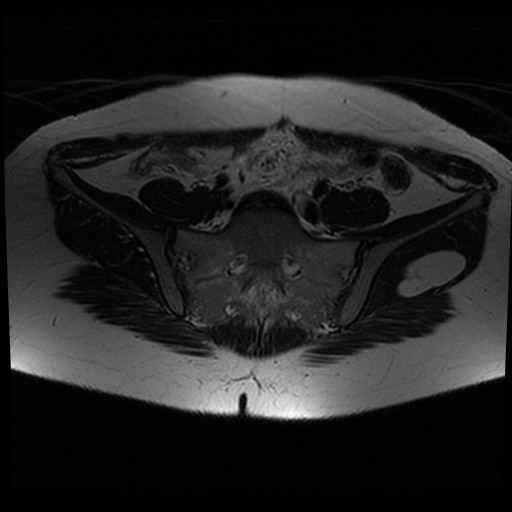

Bekken